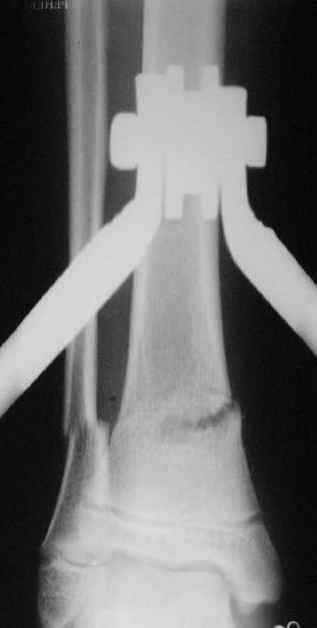

Скелетное вытяжение за пяточную кость.

A> Скелетное вытяжение за пяточную кость.

Вытяжение

|